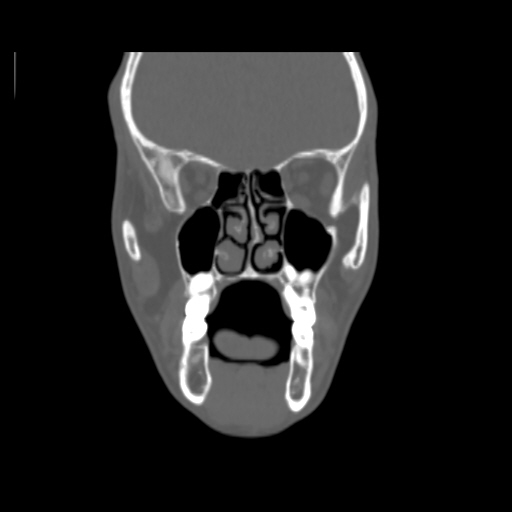

O/E images: